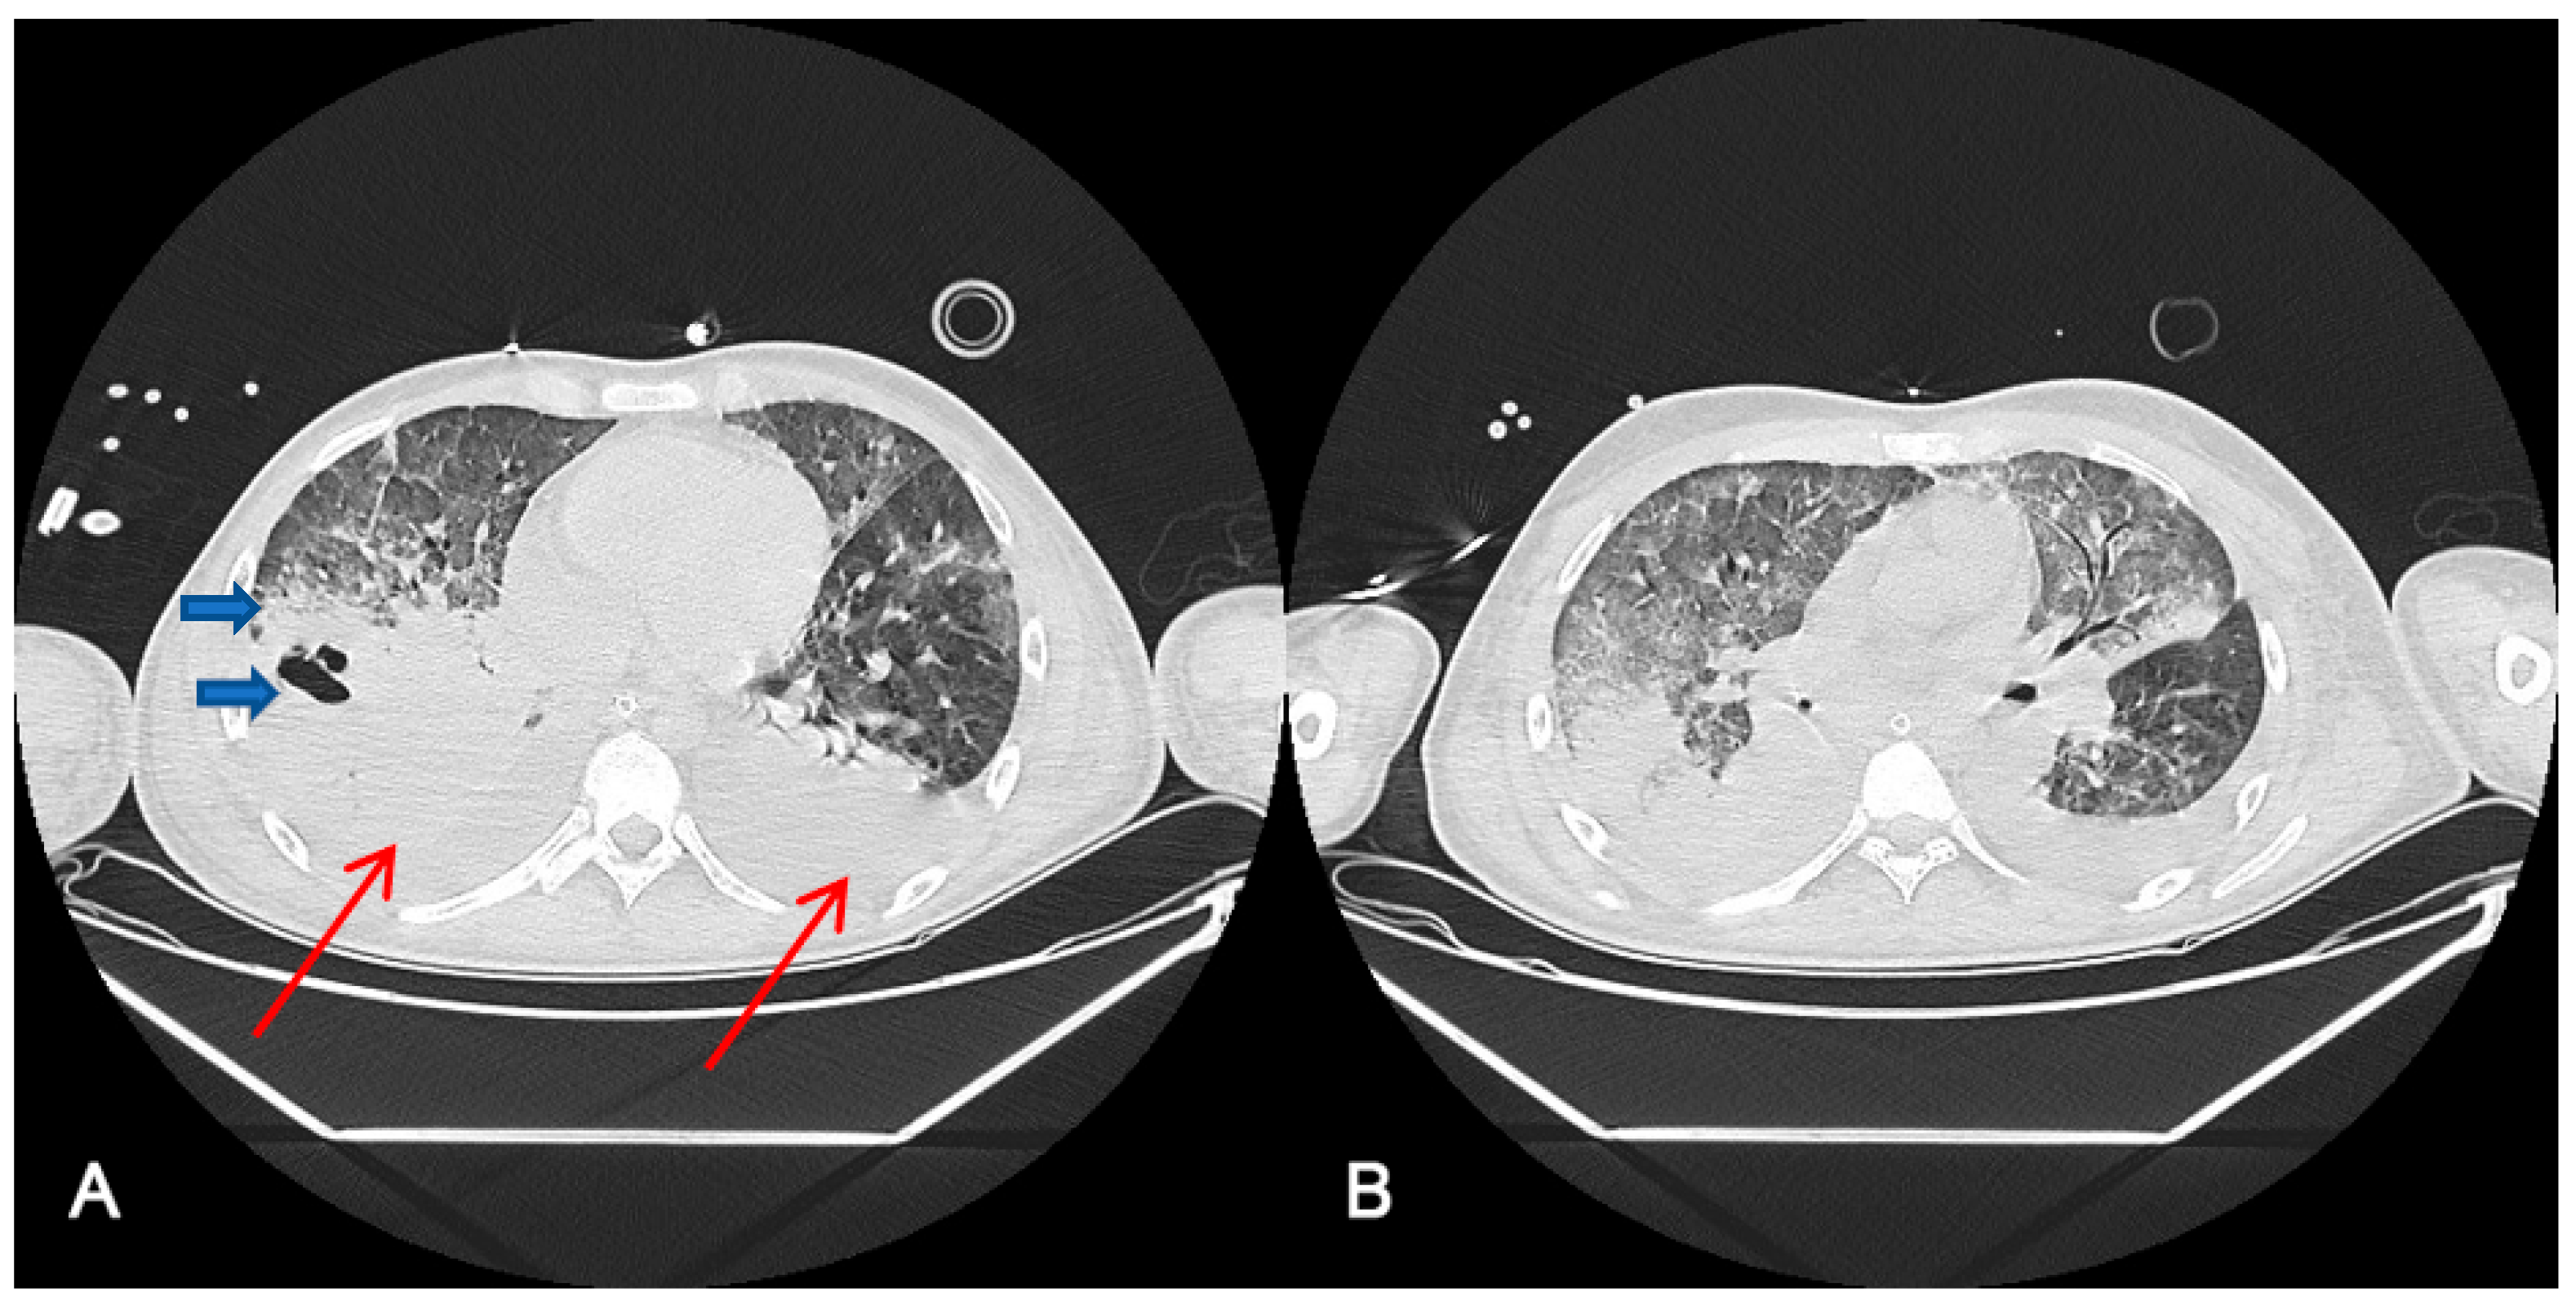

3.3. Radiological Findings